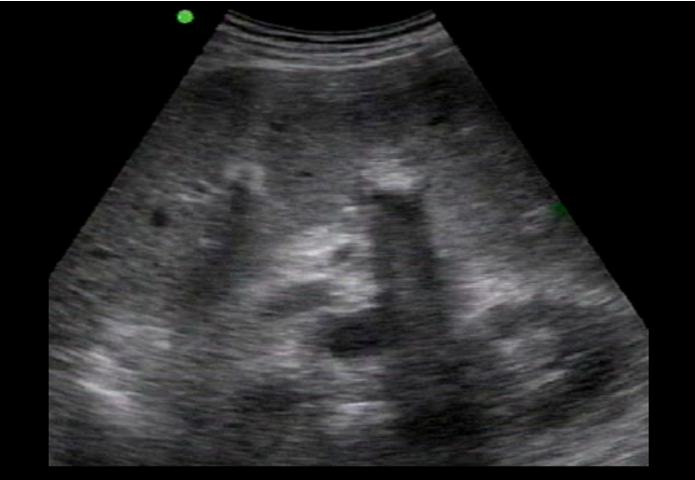

Gallbladder Bowel Gas Image